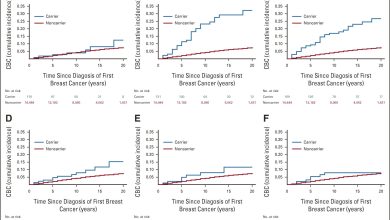

Pesquisadores identificam mulheres com risco duas vezes maior de câncer em ambas as mamas

Incidência cumulativa de risco de CBC em portadores de PV. Gráficos de incidência cumulativa para os primeiros cânceres de mama…